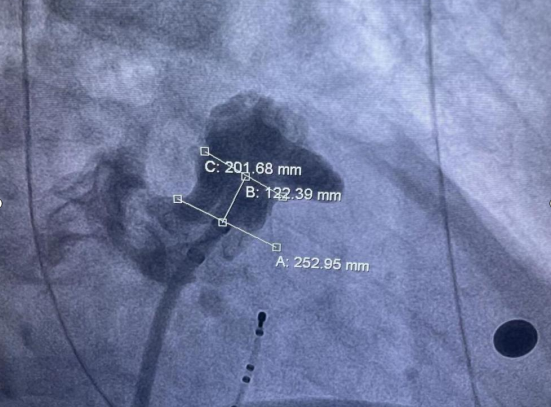

7月24日,彭学军主任团队在介入科等相关科室的密切配合下,彭林林、田鑫主任医师、邓策主治医师成功为该患者实施了房颤射频消融术+左心耳封堵术,这也是湘西州首例“一站式”房颤治疗。术后患者恢复良好,心电图示窦性心律,无不适症状。